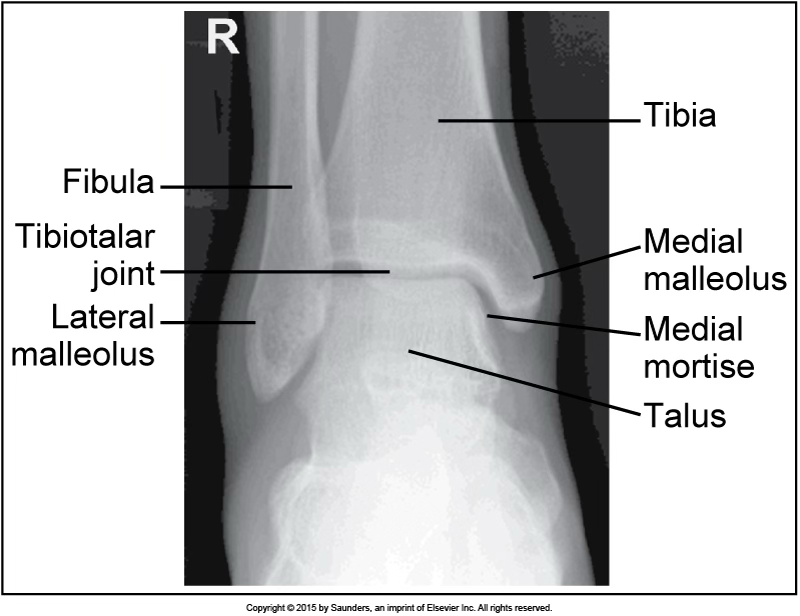

AP ankle

accurate positioning